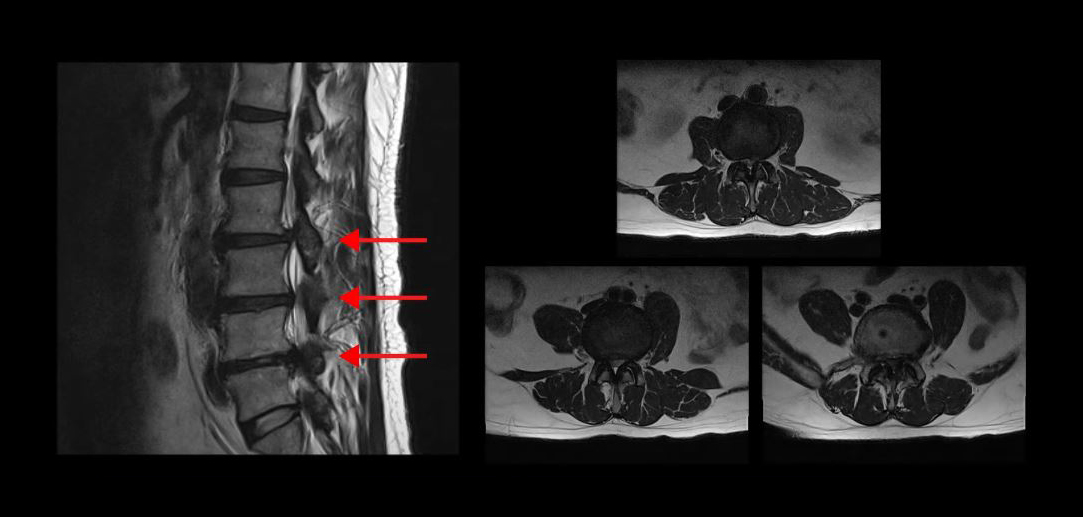

실제로 척추관이 심하게 막힌 환자분들의 케이스를 보여드리겠습니다

이분은 무려 세 마디의 척추관이 심하게 막혀있어서 거의 걷지 못하는 분입니다. MRI상 이렇게 세 마디의 척추관이 심하게 막힌 것이 보이실 겁니다. 이분은 무려 25년간 허리통증과 협착증 증상으로 고생하셨습니다. 그런데 서울 최상급 대학병원에서는 여러 마디가 안 좋으니 어려운 수술이고 수술의 실익이 없다는 말을 들으셨고, 서울 유명 척추전문병원에서는 세 마디를 한번에 수술할 수 없으니까 3주에 걸쳐 세 번의 수술을 하자는 말을 들으셨습니다.